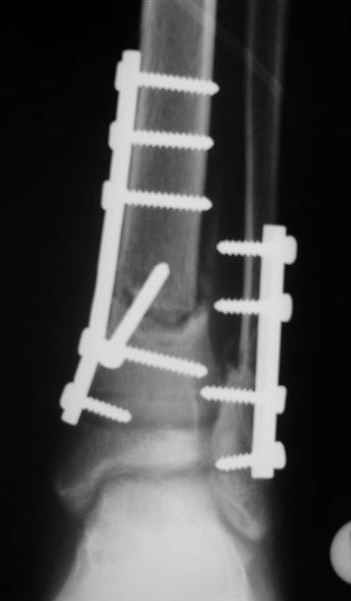

Re: дистальный тиб.фиб. перелом

Помятуя наш недавний разговор о фиксации м.б. кост, высылаю послеоперационные картинки..

Напомню- разбирали случай 17 летнего молодого человека перелом дист тиб.фиб. хирургия после 3 недель с момента травмы( безуспешные попытки закрытой репозиции) Раны заживают первичным натяжением, занимается физиотерапией, пока никаких проблем не наблюдается